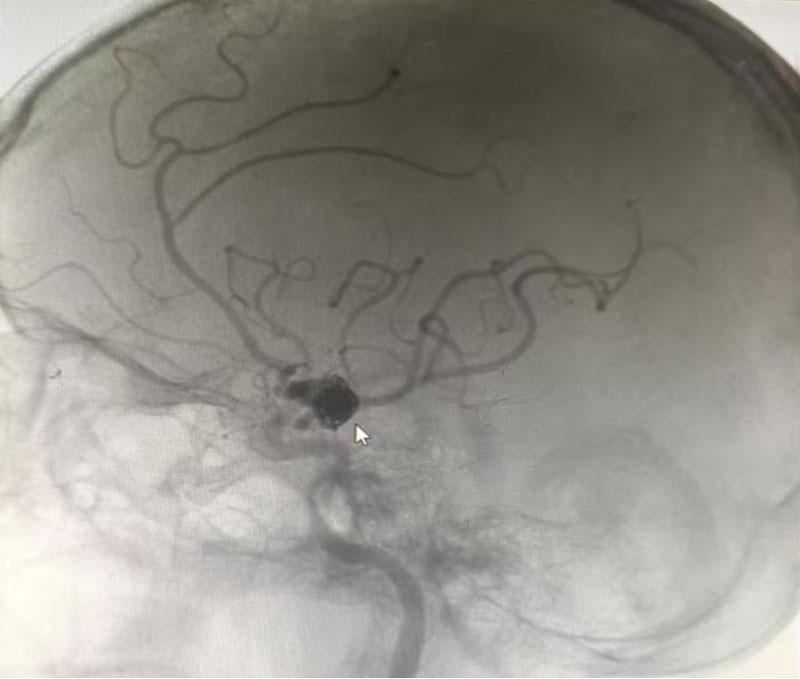

術(shù)中證實(shí)了出血原因?yàn)橛覀?cè)頸內(nèi)動(dòng)脈后交通段動(dòng)脈瘤,而華奶奶的動(dòng)脈瘤不僅體積巨大,且位置特殊,緊鄰重要神經(jīng)和血管,手術(shù)難度和風(fēng)險(xiǎn)都極大。與患者親屬深入溝通,最終確定雙微導(dǎo)管單純彈簧圈栓塞的手術(shù)方案。在省立醫(yī)院神經(jīng)外科馮斌主任醫(yī)師的指導(dǎo)下,麻醉科和介入科密切配合,由神經(jīng)外科副主任醫(yī)師王勇實(shí)施手術(shù)。術(shù)中克服了患者動(dòng)脈硬化嚴(yán)重、三型弓等困難。整個(gè)手術(shù)過程順利,術(shù)畢造影顯示動(dòng)脈瘤栓塞致密,瘤頸后的動(dòng)脈均保留完好。